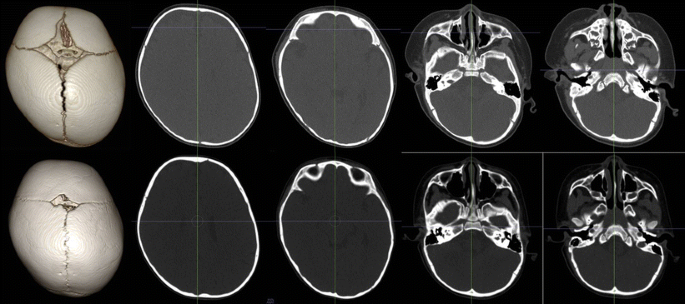

يُعاني كثير من الأطفال الرضع من مشكلة تسطّح الرأس الموضعي أو ما يُعرف طبيًا بـ تشوّه الجمجمة الموضعي. تحدث هذه المشكلة غالبًا بسبب النوم لفترات طويلة على جانب واحد من الرأس، مما يؤدي إلى ظهور جانب مسطّح أكثر من الآخر، وقد يظهر معه بعض التغيرات مثل بروز الجبهة أو الأذن أو الخد. ورغم أن الأمر قد يبدو بسيطًا في البداية، إلا أنّ القلق على مظهر الطفل وتناسق وجهه أمر طبيعي عند كل الأهل.

من أكثر الطرق الطبية شيوعًا وفعالية لعلاج هذه المشكلة: العلاج بالخوذة الطبية، الذي أثبت نجاحه في إعادة تشكيل الجمجمة وتحسين تناسق الوجه. في هذا المقال، سنجيب عن الأسئلة التي تدور في ذهن الأهل حول فعالية العلاج، أفضل وقت للبدء به، مدته، أمانه، وتجربته العملية.

الخوذة الطبية تُصمَّم خصيصًا لرأس كل طفل. تعمل من خلال ضغط لطيف ومتوازن على مناطق محددة من الجمجمة، مع ترك مساحات فارغة في المناطق المسطّحة لتسمح بنمو طبيعي. بهذه الطريقة، يُعاد توزيع نمو الرأس تدريجيًا ليصبح أكثر تناسبًا وتناظرًا.

ولا يقتصر دور الخوذة على شكل الرأس فقط، بل يساعد العلاج أيضًا في تحسين ملامح الوجه مثل توازن الجبهة والخد والأذن، مما يُعطي مظهرًا أكثر تناسقًا للطفل.

كيف يقيس الأطباء فعالية العلاج بخوذة الرأس المسطح؟

يعتمد الأطباء على فحوصات دقيقة لتقييم حالة الطفل قبل وأثناء العلاج، من أهمها:

مؤشر عدم التماثل عند مستوى الحافة السفلية للحجاج (CVAIIOR-MF).

مؤشر عدم التماثل عند الحافة العلوية للحجاج (CVAISOR-LC).

مؤشر عدم التماثل في الجزء العلوي من الرأس (CVAIMID-UC).

قياسات الأذن (D EAR) لتحديد تموضع الأذن بدقة.

هذه المؤشرات تسمح للأطباء بمتابعة تحسن شكل الجمجمة والوجه بشكل موضوعي، وتؤكد أن العلاج يُحقق نتائج واضحة، خاصة عند البدء قبل عمر السنة.